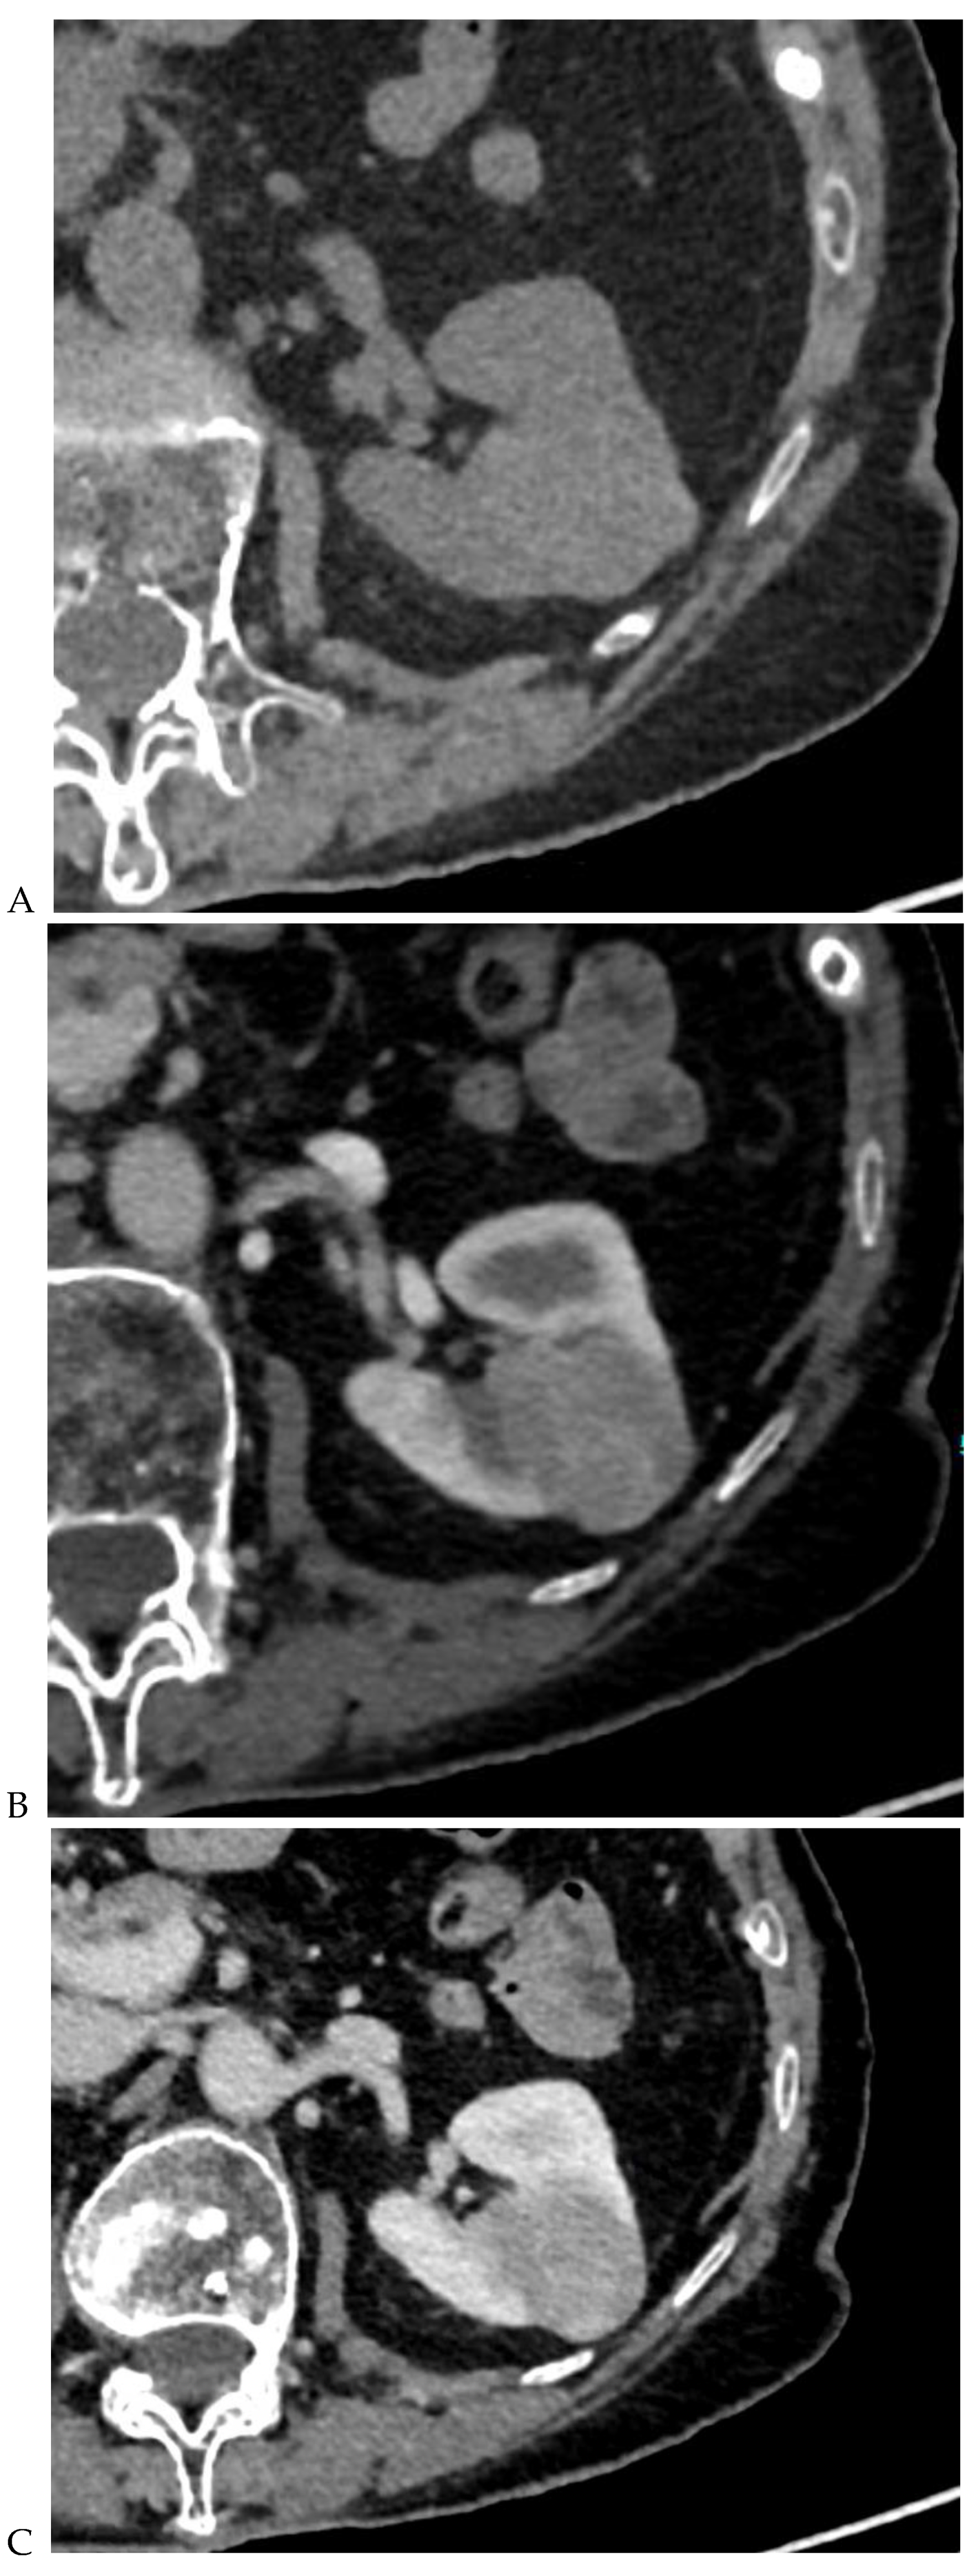

Figure 3.

CT aspect of a chromophobe renal cell carcinoma in the left kidney of a 68-year-old-woman. (A) Unenhanced image. Presence of an isodense, homogeneous solid lesion at the medium part of the left kidney. (B) It appears moderately hypervascularized on the corticomedullary phase image, with hyperdense septa. (C) There is progressive washout on the nephrographic phase image and the lesions appears hypodense relative to the renal parenchyma (C). (D) Macroscopic view of the lesion after partial nephrectomy. Courtesy of Pr S. Ferlicot, Department of Pathology, Bicêtre Hospital.

Figure 4.

Multiphasic CT enhancement of a papillary renal cell carcinoma in the middle part of the right kidney of a 63-year-old woman. (A) Mean unenhanced attenuation was 35 HU. (B) Mean corticomedullary phase attenuation was 45 HU. (C) Mean nephrographic phase attenuation was 59 HU. (D) Mean excretory phase attenuation was 65 HU.